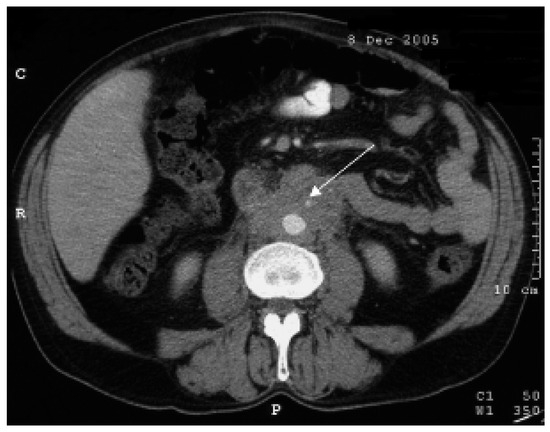

M. Ormond (retroperitoneale Fibrose)

by Y. Suter, A. Cornelius and D. Conen

Ein 49jähriger Patient stellte sich mit seit zwei Monaten anhaltenden rezidivierenden kolikartigen Oberbauchschmerzen vor. Es wurde bei Cholezystolithiasis eine Cholezystektomie durchgeführt. Während der Hospitalisation fiel eine Erhöhung der Transaminasen ohne sonographisches Korrelat auf. Eine postoperative Computertomographie des Abdomens liess ein retroperitoneales Hämatom vermuten [...] Read more.

Ein 49jähriger Patient stellte sich mit seit zwei Monaten anhaltenden rezidivierenden kolikartigen Oberbauchschmerzen vor. Es wurde bei Cholezystolithiasis eine Cholezystektomie durchgeführt. Während der Hospitalisation fiel eine Erhöhung der Transaminasen ohne sonographisches Korrelat auf. Eine postoperative Computertomographie des Abdomens liess ein retroperitoneales Hämatom vermuten (Abb. 1). [...] Full article